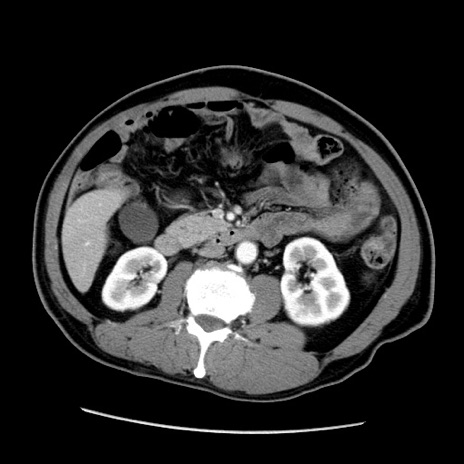

冠状断像

【症例】50歳代男性

【主訴】腹痛

【現病歴】AVMからの被殻出血のため回復期リハ病棟入院中。 本日午後3時頃急に下腹部痛が出現した。

【既往歴】AVM、被殻出血、虫垂炎、高血圧

【身体所見】意識晴明、左半身不全麻痺、会話の理解は良好、36.5°C、腹部:膨隆、全体に板状硬、下腹部正中に圧痛点あり、反跳痛-、筋性防御不明、右下腹部にope scar

【データ】WBC 9400、CRP 0.06